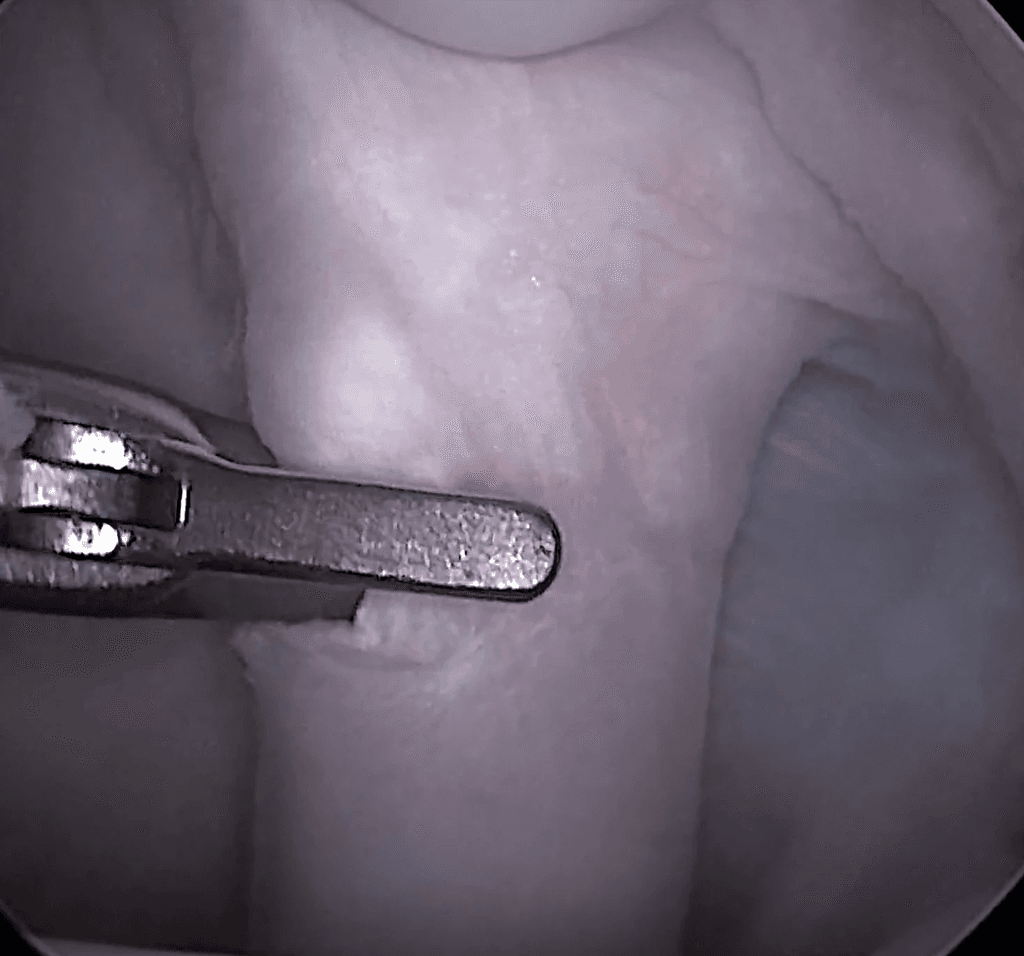

Fragment Removal

Fragment removal can be performed minimally invasively with arthroscopy or through a small open approach. Removing the fragment is the most consistent way to resolve lameness and reduce the risk of long-term joint issues. In rare cases with very large defects, a cartilage resurfacing technique may be considered, though this is seldom necessary.